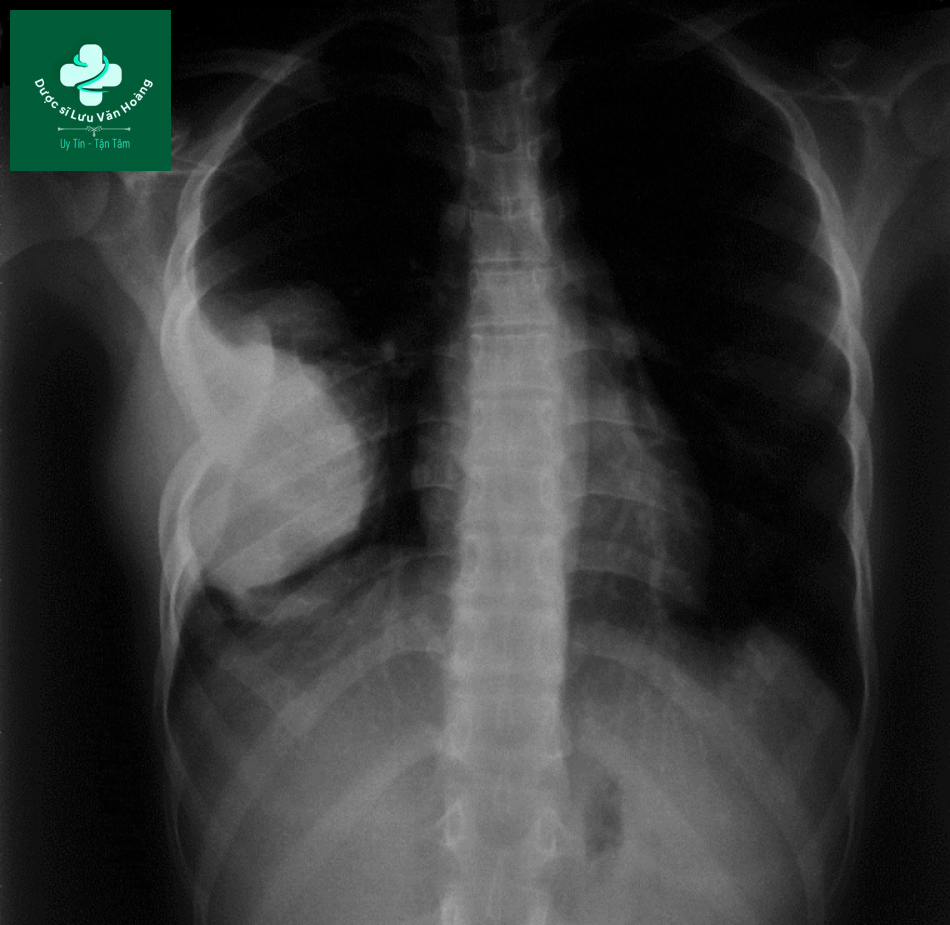

Bệnh nhân nữ, 15 tuổi, ho khan, khó thở và sút cân 2 tháng nay, không sốt. Phim x-quang cho thấy hình mờ toàn bộ lồng ngực trái, đè đẩy trung thất sang phải.